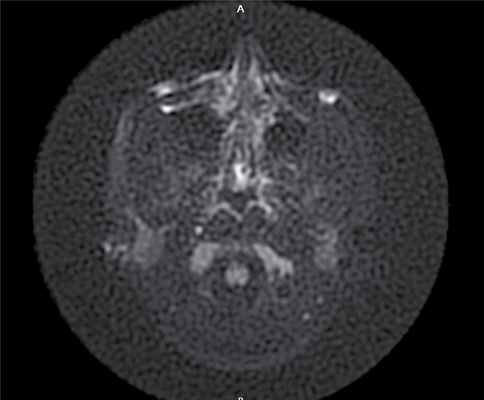

МРТ среднего уха — в области нижней и задней граней пирамиды височной кости инфралабиринтно визуализируется образование размером 15,6×26×20 мм, прилежит и компримирует внутреннюю яремную вену, характеризуется преимущественно гиперинтенсивным сигналом в Т2, STIR, умеренно гиперинтенсивным в Т2 flair, изоинтенсивным в Т1 ВИ, с повышением сигнала на DWI с коэффициентом В 1000 и вычитанием на ИКД-картах, что соответствует холестеатомным массам.

Через 6 мес по результатам отомикроскопии, МСКТ височных костей, МРТ среднего уха в DWI-режиме: в сосцевидном отростке, в аттико-антральной области, в области нижней и задней граней пирамиды височной кости визуализируется обширная послеоперационная полость; в барабанном и мастоидальном сегментах послеоперационной полости пристеночно визуализируется содержимое умеренно неоднородной структуры, гетерогенного МР-сигнала в Т2 ВИ, STIR, T2 flair, изоинтенсивное в Т1 ВИ, без повышения сигнала на DWI c коэффициентом В 1000 и вычитанием на ИКД-картах (вероятно, рубцово-фиброзные изменения): данных за рецидив холестеатомы получено не было (рис. 4). Рис. 4. МР-томограмма среднего уха, выполненная в DWI- режиме.